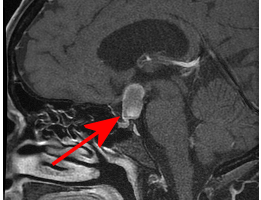

sagittal section showing craniopharyngioma

Craniopharyngioma

Some differential considerations for a partially cystic sellar/suprasellar mass include a cystic macroadenoma, Rathke’s cleft cyst, cranipopharyngioma, aneurysm, arachnoid cyst and epidermoid. Read more »